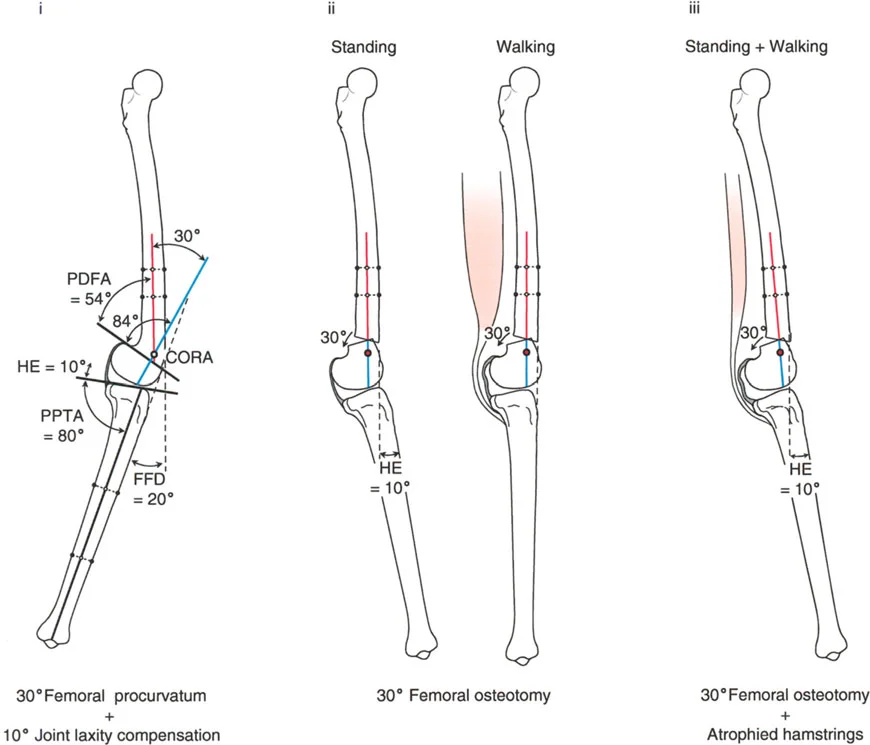

- تحدُّد حركة الركبة (Flexion Deformity - FFD): عدم القدرة على مد الركبة بالكامل، بحيث تظل الركبة في وضعية انثناء جزئي حتى عند محاولة فردها. يمكن أن يكون هذا ناتجًا عن تشوهات عظمية (مثل تقوس عظم الفخذ أو الساق للأمام) أو تقلصات في الأنسجة الرخوة (الأوتار والعضلات).

- الركبة الارتدادية (Recurvatum Deformity - Hyperextension): تمدد الركبة بشكل مفرط للخلف (فرط البسط)، أي تجاوز نقطة الاستقامة الطبيعية. يمكن أن يكون هذا ناتجًا عن ضعف العضلات (خاصة أوتار الركبة) أو تشوهات عظمية.

تصحيح تحدد حركة الركبة (Flexion Deformity - FFD)

تحدُّد حركة الركبة هو عدم القدرة على مد الركبة بالكامل. يمكن أن يكون سببه عظميًا أو ناتجًا عن تقلص في الأنسجة الرخوة.

- التشخيص الدقيق: يجب تحديد ما إذا كان تحدد الحركة ناتجًا عن تشوه عظمي (تقوس أمامي في الفخذ أو الساق) أو تقلص في الأنسجة الرخوة (الأوتار الخلفية، محفظة المفصل).

- قطع العظم التمديدي (Extension Osteotomy):

- إذا كان التشوه عظميًا، يتم إجراء قطع عظم تمديدي في عظم الفخذ أو الساق لتصحيح التقوس.

- الأستاذ الدكتور محمد هطيف يؤكد على أهمية عدم تصحيح الساق بأكثر من 90 درجة PPTA لتجنب فقدان الميل الخلفي الطبيعي للساق.

تصحيح الركبة الارتدادية (Recurvatum Deformity - Hyperextension)

الركبة الارتدادية هي فرط البسط في الركبة. غالبًا ما تكون غير مصحوبة بأعراض في الأشخاص ذوي العضلات السليمة، ولكنها قد تسبب مشاكل في حالات ضعف العضلات أو التشوهات العظمية.

- التشخيص: يجب تحديد ما إذا كانت الارتدادية عظمية (تقوس خلفي في الفخذ أو الساق) أو ناتجة عن رخاوة في الأنسجة الرخوة أو ضعف عضلي.

- قطع العظم الانثنائي (Flexion Osteotomy):

- إذا كان التشوه عظميًا (تقوس خلفي)، يتم إجراء قطع عظم انثنائي في عظم الفخذ أو الساق لتصحيح الارتدادية.

- الأستاذ الدكتور محمد هطيف يشدد على أهمية عدم استخدام قطع عظم الفخذ الانثنائي لتصحيح ارتدادية الساق، والعكس صحيح، لتجنب الانزلاق الخلفي أو الأمامي للركبة.

- اعتبارات خاصة: في المرضى الذين يعانون من ضعف عضلي (مثل شلل الأطفال)، قد يحتاج التصحيح إلى فرط تصحيح بسيط (overcorrection) إلى وضعية انثناء لضمان ثبات الركبة ومنع فرط البسط غير المتحكم فيه.